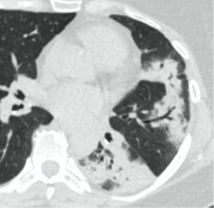

Методы лучевой диагностики применяют для выявления COVID-19 пневмоний, их осложнений, дифференциальной диагностики с другими заболеваниями легких, а также для определения степени выраженности и динамики изменений, оценки эффективности проводимой терапии.

К методам лучевой диагностики патологии ОГК пациентов с предполагаемой/установленной COVID-19 пневмонией относят:

- Компьютерную томографию легких (КТ),

КТ имеет высокую чувствительность в выявлении изменений в легких, характерных для COVID-19. Применение КТ целесообразно для первичной оценки состояния ОГК у пациентов с тяжелыми прогрессирующими формами заболевания, а также для дифференциальной диагностики выявленных изменений и оценки динамики процесса. КТ позволяет выявить характерные изменения в легких у пациентов с COVID-19 еще до появления положительных лабораторных тестов на инфекцию с помощью МАНК. В то же время, КТ выявляет изменения легких у значительного числа пациентов с бессимптомной и легкой формами заболевания, которым не требуется госпитализация. Результаты КТ в этих случаях не влияют на тактику лечения и прогноз заболевания при наличии лабораторного подтверждения COVID-19. Поэтому массовое применение КТ для скрининга асимптомных и легких форм болезни не рекомендуется.